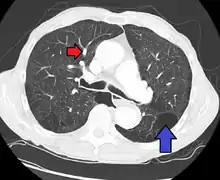

CT scan

Pulmonary artery hypertension and emphysema as seen on a CT scan with contrast

Signs of pulmonary hypertension on CT scan of the chest are:

• Increased ratio of the diameter of the main pulmonary artery (pulmonary trunk) to the ascending aorta (measured at its bifurcation).

• A ratio of 1.0 is suggested as a cutoff in adults.[62]

• Cutoff ~1.09 in children.[62]

• Increased diameter ratio of segmental arteries to bronchi. This finding in three or four lobes, in the presence of a dilated pulmonary trunk (≥29 mm), and absence of significant structural lung disease confers a specificity of 100% for pulmonary hypertension.[62]

• Mural calcification in central pulmonary arteries is most frequently seen in patients with Eisenmenger's syndrome.[62]